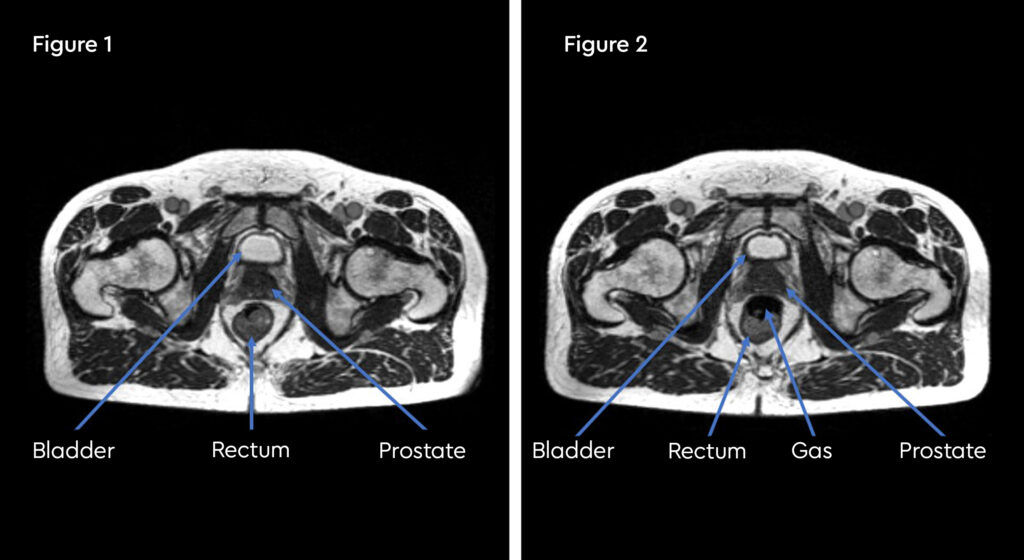

Figure 1 and figure 2 illustrate the typical interfraction movement as seen on the MRI scan. Figure 3 and figure 4 demonstrate the daily changes of the patient’s internal anatomy whilst figure 5 and figure 6 show the adaptive radiotherapy plan.

Fig 1: Internal anatomy during the planning MRI

Fig 2: Internal anatomy during first fraction of treatment

Fig 3: Changes in internal anatomy demonstrated by a smaller rectum on day 3 compared to the planning scan

Fig 4: Changes in internal anatomy demonstrated by a different rectum size on day 4